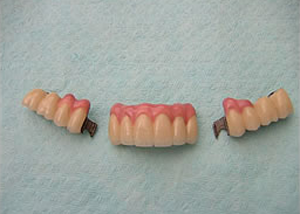

9.模型上の最終物

10.3ケのユニットになっています。

11.最終の作った歯が入った後の口腔内